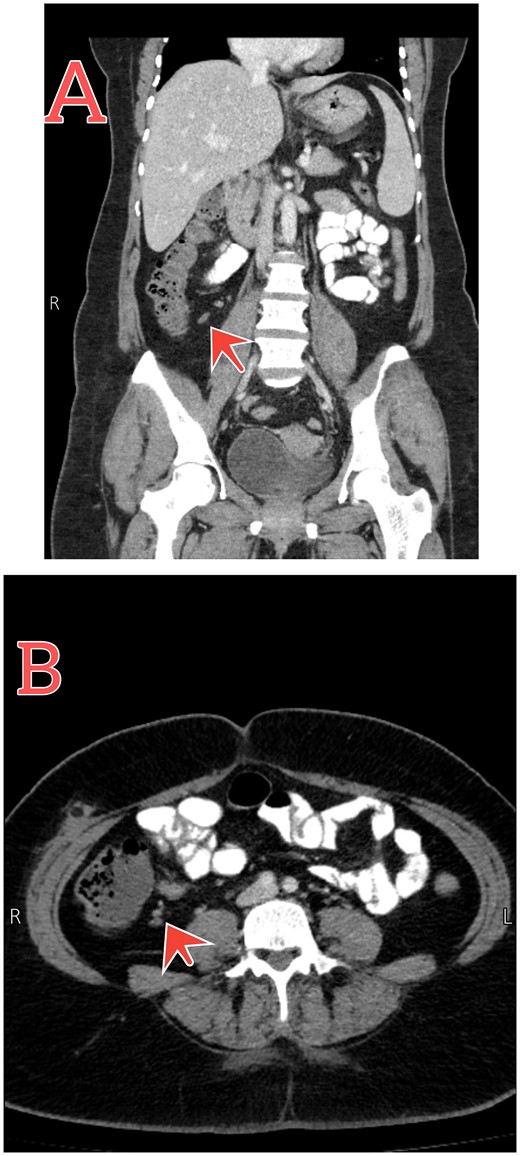

Further investigations were done to confirm the diagnosis, CBC showed elevated WBC with left shifting, and C-reactive protein (CRP) was positive at 16 g/l. gynecological consulted to exclude any gynecological cause, the ultrasound was free. Urine analysis was done, and it was free. For that, with the history of initial appendectomy, subsequent abdomen, and pelvic computed tomography (CT) with contrast was performed. Findings represent inflammation of the distal part of the residual appendix associated with mucosal enhancement and mild surrounding fat stranding, confirming the diagnosis of recurrent tip appendicitis (Fig. 1).

Abdomen–pelvic CT scan shows tip appendicitis. (A and B) Coronal and axial sections show the distal part of a blind-ended tubular structure measuring about 8 mm arising from the cecum (red arrows), associated with mucosal enhancement and mild surrounding fat stranding.